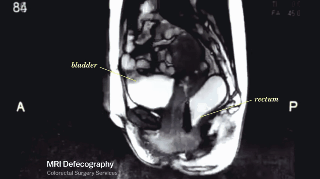

2. Haciendo la digestión, donde se puede ver la vejiga y el recto humano.